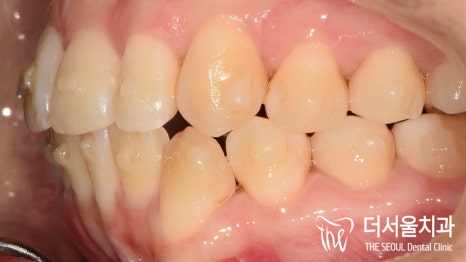

측면에서 바라보니,

앞으로 더 많이 뻐드러져 있는 것이 확인이 되죠?

이런 증세들 때문에

입술이 튀어나온 것 처럼 보여지게 되는 겁니다.

측면에서 바라봤을 때에도, 전과는 다르게

뻐드러짐이 없어진 것이 확인 됩니다.